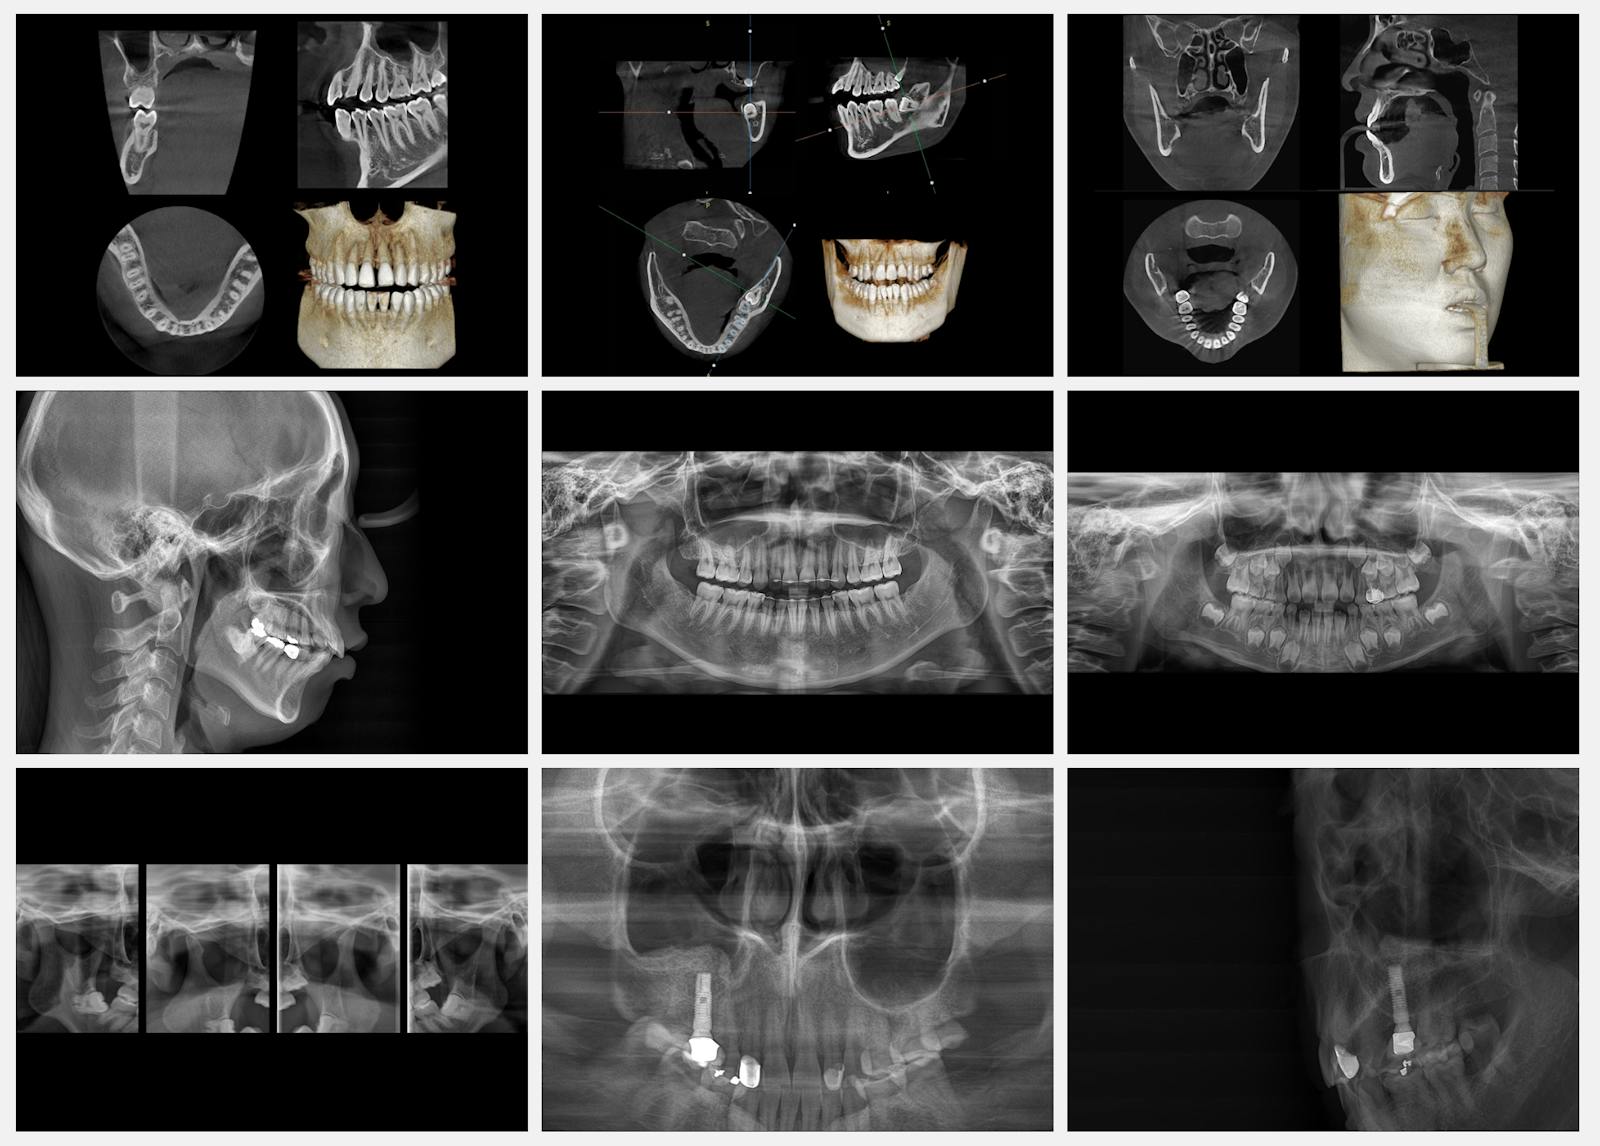

Реальні КТ-дослідження

Сучасне програмне забезпечення «Theia»

Зручне в користуванні програмне забезпечення з інтуїтивним інтерфейсом дозволяє працювати з 3D зображеннями в режимі реального часу